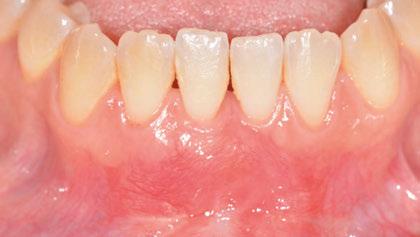

Figura 1. Caso clínico 1. Situación clínica basal de una paciente que presenta recesiones gingivales con pérdida de inserción interproximal en el quinto sextante. A la exploración se observa una profundidad de sondaje incompatible con salud en centro-vestibular del diente en posición de 41, presumiblemente combinado con una dehiscencia ósea.

Paciente de 32 años de edad que acude a la consulta preocupada por la situación de su diente en posición de 41. Le preocupa tanto a nivel de salud como a nivel estético. Además, refiere incapacidad para llevar a cabo un correcto cepillado de esa zona e hipersensibilidad dental.

A la exploración clínica presenta una recesión RT3 (23) en el diente en posición de 41. Además, carece de una banda de encía queratinizada adecuada (≥2mm) y presenta una reducción significativa de la

profundidad de vestíbulo combinada con la inserción alta y/o aberrante del frenillo labial incapacitando un correcto mantenimiento de la zona (24).